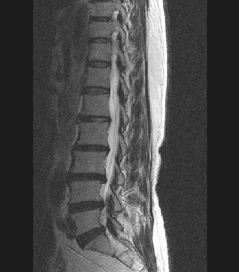

• 척추 방사선 사진2

64세 여자환자는 2개월 전부터 요통과 다리 바깥쪽과 발등, 종아리 뒤쪽으로 저린 감각이 심해져서 개인병원에 들러 평가 및 물리치료를 받았으나 별다른 호전이 없고, 1주일 전부터는 허리를 숙이거나 물건을 들 때, 오래 걸을 때 통증이 더 심해져서 본원을 방문하였다. 12년전 집안일을 심하게 하고 난 후부터 간헐적인 요통을 발생하였으며, 별다른 치료 없이 지냈으며, 4년전 무거운 물건 들고 난 후 심하게 요통과 둔부의 통증까지 발생하여 MRI 촬영상 L1-2, L3-4-5, L5-S1 HNP와 Lt. L4 & both L5 nerve compression, Lt. S1 nerve compression 진단받고 Epidural steroid injection을 받고 통증 경감되었고, 간헐적으로 통증이 발생하였으나 별다른 치료 없이 헬스클럽에서 지속적인 운동으로 관리하였다.